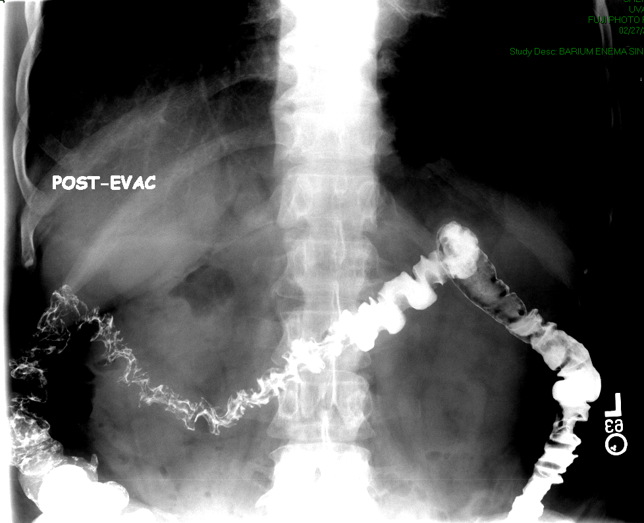

- When the patient has finished using the restroom, the technologist will obtain a post evacuation overhead radiograph

(key image 18)

(key image 19).

- For most patients only an AP radiograph is needed; however, additional images may be needed based on the patient's history or findings during the examination.